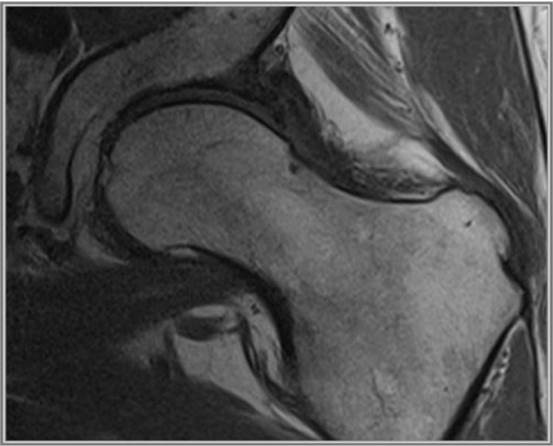

En la exploración física se evidencia dolor inguinal a la movilización activa y pasiva, acentuándose en rotación interna y aducción de la cadera; disminución del arco de movilidad en flexión y rotación externa. Signo de Drehmann y test impigement positivos. Se decide pautar antiinflamatorios y solicitar radiografía simple de cadera antero-posterior, en la que se evidencia esclerosis subcondral, osteofitos, “giba lateral” (“pistolgrip": deformidad en mango de pistola) con pinzamiento femoroacetabular, deformidad de cabeza y rotura del labrum acetabular (Figura 1). Dados los hallazgos, se decide derivar a los pacientes a Reumatología donde, tras la valoración, deciden solicitar RM de caderas, que confirma los cambios degenerativos junto con necrosis avascular grado III de la cabeza femoral izquierda, signos diagnósticos de un síndrome femoroacetabular tipo CAM (Figura 2). Actualmente ambos pacientes presentan una limitación para la deambulación con antiinflamatorios pautados de forma crónica.